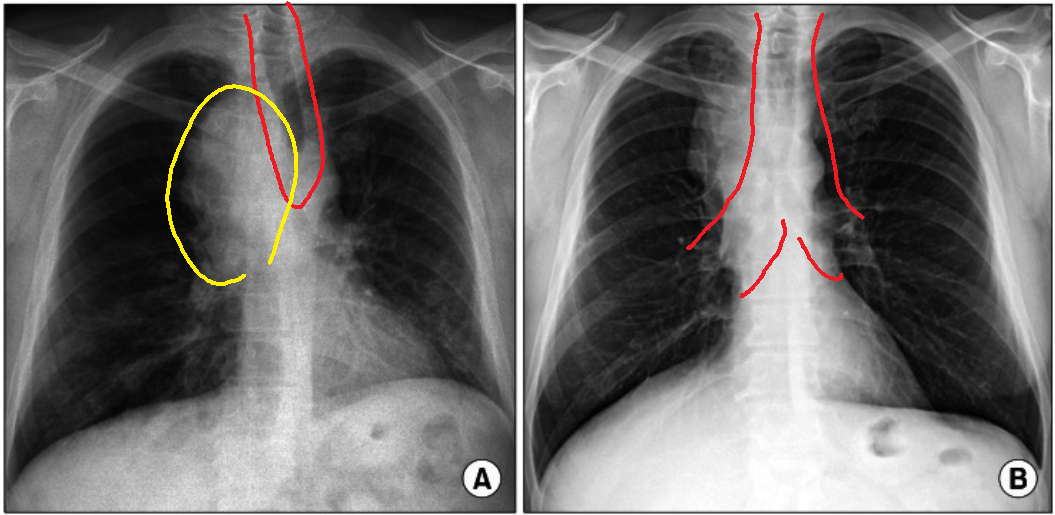

- CT ratio: Cardio-thoracic ratio

심장의 크기를 확인하기 위한 방법으로 흉곽의 너비 대비, 심장의 너비를 비교한다. 일반적으로 chest PA에서는 CT ratio가 50% 이하로. 측정되어야 정상이며, 50% 초과의 경우엔 심비대(cardiomegaly)를 의심할 수 있다.

다만 CT ratio의 경우엔 chest PA보다 chest AP에서 증가되는 소견이 있으므로, 위 0.5라는 기준은 chest PA기준임을 잊지 말자.

- Mediastinum: 종격동

종격동은 흉부의 좌우 폐의 가운데 공간으로, 아래 그림처럼 심장이 주로 자리 잡고 그 위로는 식도와 기관(trachea)이 있으나 x ray에서는 심장에서 나온 대동맥궁(aortic arch)이 종격동의 좌측 경계를 상대정맥(SVC, superior vena cava)이 종격동의 우측 경계를 형성하게 된다.

따라서 종격동의 확장(mediastinum widening) 소견이 확인된다면, 대동맥류와 같은 혈관이 커지는 질환을 의심해봐야 한다.